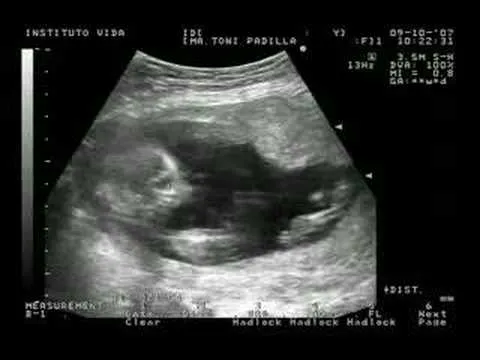

Ecografías de 16 semanas de embarazo varón

Descubre imágenes de ecografías de 16 semanas de embarazo varón, perfectas para ver el desarrollo fetal y compartir la emoción del embarazo.

Ecografia de 16 semanas de embarazo - Imagui